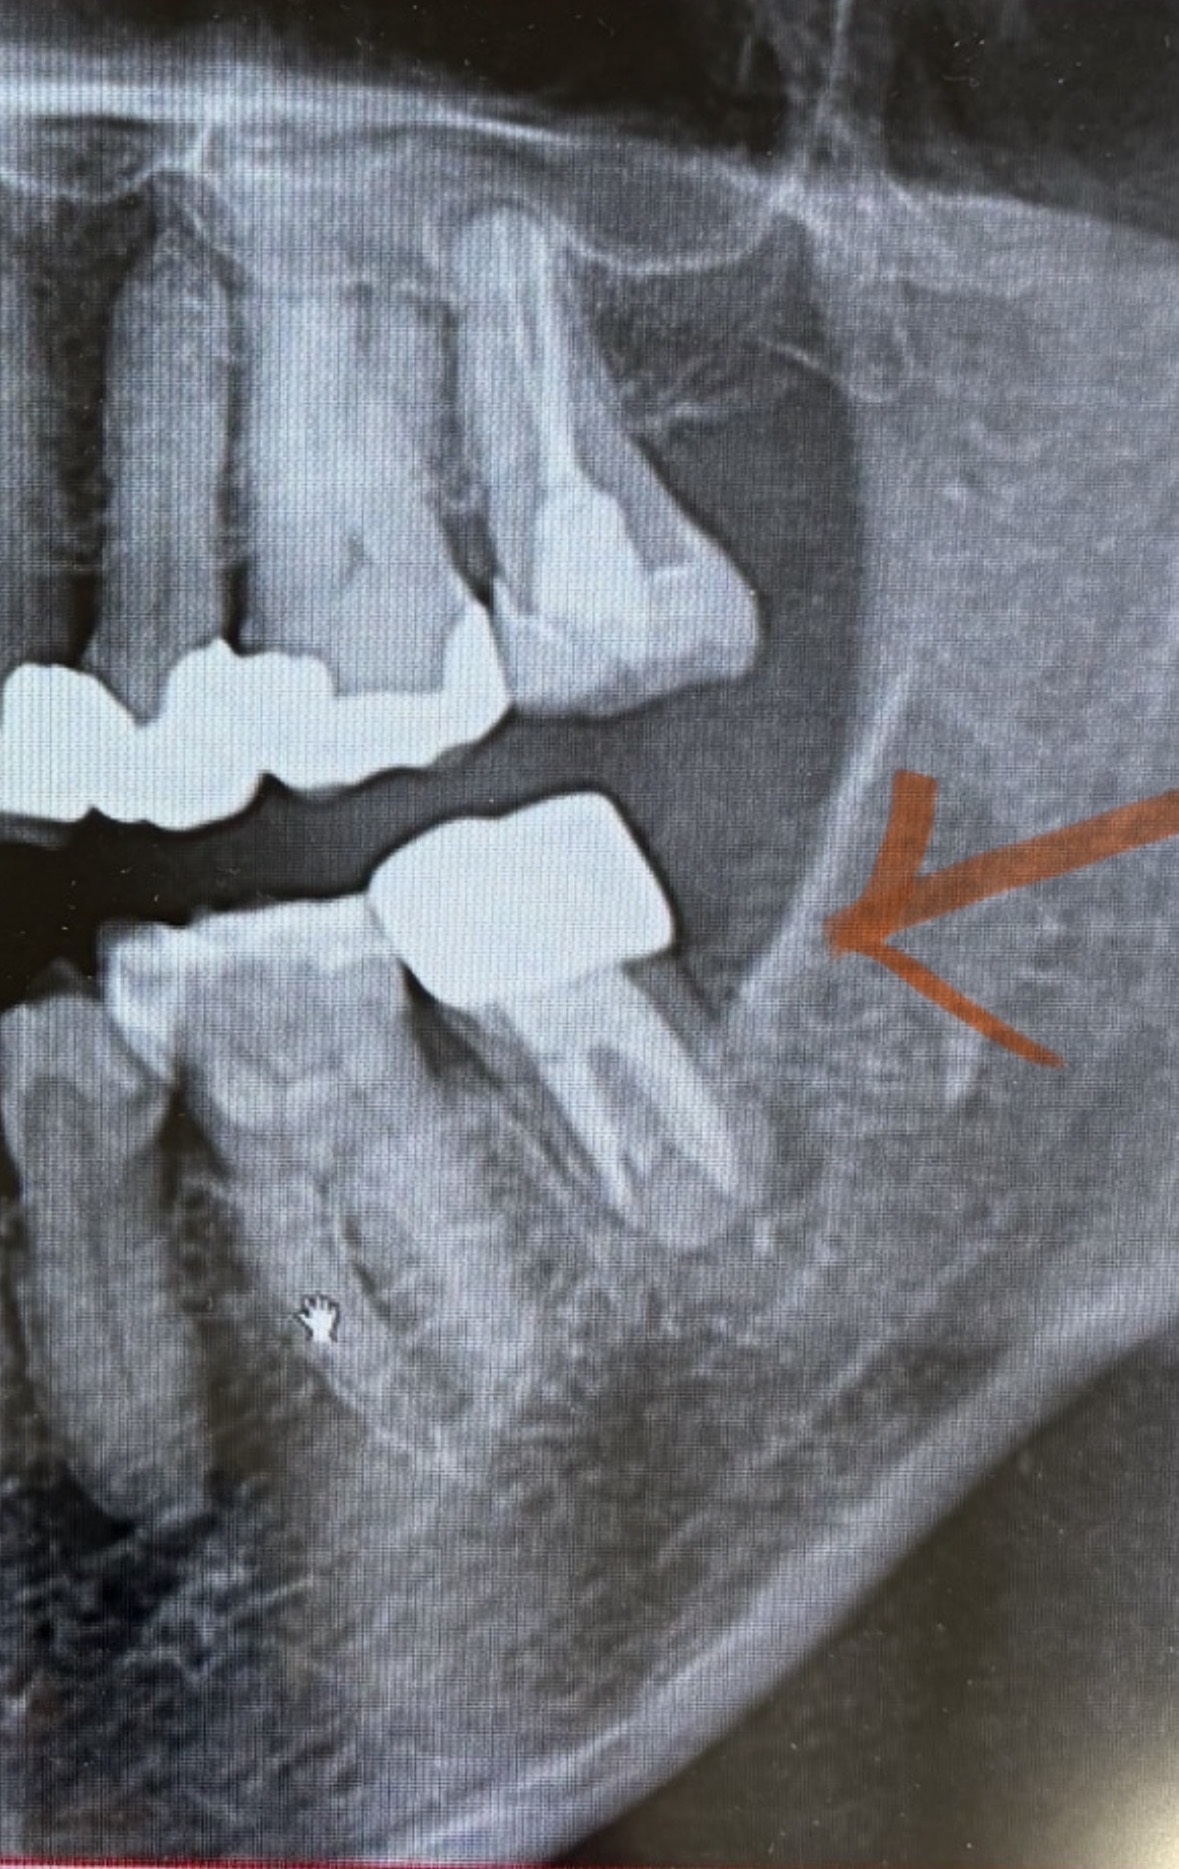

CTがその歯科医院はないので、あるところじゃないと判断つかないでしょうか?

その前にどこかCTを撮っていただき、それを持参して判断してもらう方がいいですか?

>CTがその歯科医院はないので、あるところじゃないと判断つかないでしょうか?

>どこかCTを撮っていただき、それを持参して判断してもらう方がいいですか?

機種やモードによって繊細さが異なりますし、そもそも読影力の差異に大きく左右されますので、このケースの場合でしたら、無いより有れば、といった程度のように思います。

歯が弱っているというより、添付された写真から察するに、歯を支えている ( た ) 骨が弱っているものと推測します。

精査してみなければ何とも言えませんが、抜歯の可能性は否定できません。